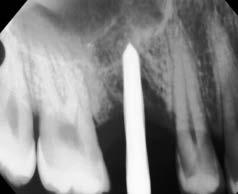

40 años acudió para la rehabilitación del sector posterior superior, pues presentaba un defecto vertical en el cuadrante superior derecho a la altura del primer molar, una altura óseorresidual de 3.5 mm y un tipo óseo III. Dadas las condiciones, se optó por la técnica de oseodensificación para la elevación del piso del seno maxilar y la preparación del lecho implantario. Entre los hallazgos descritos en los resultados se encontró una elevación sinusal de al menos 6 mm, evidenciada en las imágenes radiográficas intraoperartorias, que permitió la colocación de un implante de 5 mm de plataforma por 8 mm de longitud, ubicado 1 mm en posición subcrestal. Una tomografía

axial computarizada confirmó la situación del implante, así como la efectividad de la oseodensificación y la elevación del piso sinusal de 6 mm. la osteointegración del implante se completó sin necesidad de procedimientos quirúrgicos adicionales de mayor complejidad. Se concluye que la oseodensificación es una técnica eficaz y predecible para la osteotomía y la elevación sinusal transcrestal, favorece la estabilidad primaria del implante y constituye un procedimiento mínimamente invasivo.

Figura 2. Planeación en tomografía axial computarizada: a) vista sagital, b) vista transversal, c) vista 360°, d) reconstrucción 3D y e) ortopantomografía.

quirúrgico de elevación sinusal transcrestal y osteotomía, para optimizar la estabilidad primaria y la integración ósea en la colocación de implantes dentales endoóseos, mediante medición del torque de inserción y comprobación radiográfica que muestre la elevación sinusal y el implante colocado en el sitio requerido. Rehabilitar la zona edéntula de la paciente para restaurar la función estética y masticatoria sin recurrir a procedimientos quirúrgicos invasivos.

Al examen intraoral se observa arcada dental incompleta; con ausencia de órganos dentales 16 y 27 (Figura 1).

Planeación tomográfica

Se creó un mapeo óseo para evaluar las dimensiones de altura y anchura ósea disponibles para la colocación del implante dental y su posterior restauración protésica. El análisis reveló una cantidad reducida de tejido óseo en el piso del seno maxilar (3.61 mm), lo que condicionó la planificación del procedimiento. Para la rehabilitación implantológica, se requiere la colocación de un

implante de al menos 8 mm de altura por 5 mm de diámetro, con adecuado espacio vestíbulo-palatino e interoclusal. No obstante, luego de considerar la insuficiencia de volumen óseo en sentido vertical y el grado de neumatización del seno maxilar, se determinó que la colocación del implante mediante técnicas convencionales no era viable, por ello la necesidad de procedimientos de aumento óseo para lograr una rehabilitación adecuada (Figura 2).

Figura 3. Protocolo de fresado quirúrgico: a) fresa piloto sentido horario, b) comprobación radiográfica, c) RX pin de paralelismo, d) fresa 2.3 sentido antihorario, e) comprobación radiografía periapical de posición y elevación del piso de seno, f) fresa 3.2 a 9mm con elevación evidente, g) verificación de profundidad con sonda del kit de implantes, h) colocación de injerto de hueso NovaBone, i) vista del hueso en el lecho quirúrgico j) fresa final diámetro 4.3, k) RX de comprobación de fresa 4.3 y l) RX de implante e injerto colocados.

fresado (fresa de 4.2 mm de diámetro) dentro del sitio preparado como indica el protocolo de fresado Versah. Gracias al diseño específico de las fresas, el biomaterial fue distribuido hacia las zonas superior y lateral del sitio quirúrgico para promover una adecuada condensación ósea y facilitar la colocación del implante en una posición subcrestal de 1 mm.

Entre cada cambio de fresa, se verificó radiográficamente la dirección y profundidad del fresado. Finalmente, se completó el protocolo con el uso de la fresa de 4.2 mm de diámetro hasta alcanzar una profundidad final de 9 mm. Se obtuvieron imágenes radiográficas que evidencian la correcta colocación del injerto en la elevación lograda (ver Figura 3).

Una vez colocado el implante de la marca Adin Closefit de 5 mm de diámetro × 8 mm de largo, se lavaron profusamente la zona periferia y el interior del implante con solución fisiológica estéril. Cuando se instaló el tornillo tapa

correspondiente, se evaluó la estabilidad primaria mediante la técnica de torque de inserción y una llave dinamométrica, instrumento diseñado para medir y controlar la fuerza aplicada durante la inserción del implante. Este parámetro refleja la resistencia y rigidez de la interfase hueso-implante: a mayor torque, mayor estabilidad primaria (Figura 4).

Figura 4. Comprobación de estabilidad inicial mediante torque de inserción: a) llave dinamométrica inserta el implante a su sitio final y b) acercamiento muestra torque de inserción de 100 N·cm.

alguna. 3 meses después se valoró con ortopantomografía (Figura 5).

Resultados

Se logró una elevación sinusal de 6 mm en el sitio destinado para la colocación del implante endoóseo. Se colocó injerto sintético en la zona elevada para implantar en una única sesión quirúrgica, y se obtuvo un torque final de 100 N•cm, lo que indicó una excelente estabilidad primaria. La rehabilitación protésica se realizó sin complicación alguna, mediante una corona atornillada metal-cerámica, 2 meses después de haber colocado el implante. La integridad de la restauración se mantuvo en óptimas condiciones durante el seguimiento clínico a 5 años de la rehabilitación.

Se observaron excelentes condiciones clínicas y radiológicas, entre las que destacan: reducción de la cresta ósea menor a 1 milímetro y ausencia

de movilidad y sintomatología. La restauración es plenamente funcional y estética; la paciente refiere estar muy satisfecha, lo cual representa un éxito, con base en artículos referentes a los criterios de éxito en implantes dentales.

La Figura 6 presenta una comparación entre el estado previo a la colocación del implante y el estado actual. Se observa que, a pesar de un notable deterioro en los dientes naturales adyacentes, existe integración y funcionalidad satisfactorias, además se evidencia el aumento de volumen óseo obtenido.

Figura 5. Ortopantomografía 3 meses después de colocado el implante. Se aprecia la elevación sinusal y el hueso injertado.

Figura 6. Fotografías y radiografías iniciales y actuales: a) fotografía intraoral arcada superior inicial, b) fotografía arcada superior, abril 2025, C) ortopantomografía octubre 2024 y d) radiografía periapical abril 2025.

permitió la colocación del implante sin necesidad de recurrir a procedimientos más invasivos, lo que evidencia su utilidad en sitios con altura ósea limitada. Los hallazgos intraoperatorios y postoperatorios presentados en este artículo corroboran la eficacia de la oseodensificación, debido a que la elevación sinusal alcanzada fue de 6 mm, lo que posibilitó la colocación de un implante de dimensiones adecuadas con estabilidad primaria óptima.

Estudios previos, como los de Huwais & Meyer (2017) y Trisi et al. (2016), demuestran que esta técnica no solo aumenta la densidad ósea, sino que también contribuye a la expansión del tejido óseo y favorece la osteointegración a largo plazo.29 La capacidad de compactación ósea observada en este caso clínico es consistente con los resultados obtenidos en estudios experimentales, ya que el torque de inserción resultante de la OD y del injerto de hueso fue de 100 N·cm. Debido a que el mínimo en N·cm es de 35 para obtener una buena estabilidad primaria; se evidenció un aumento del volumen óseo notablemente visible en las radiografías del caso y en la TAC presentada.